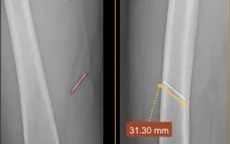

Gắp dị vật kim loại sâu do tai nạn lao động

VTV.vn - Một bệnh nhân bị tai nạn lao động, dị vật kim loại nằm sâu trong tổ chức phần mềm đùi đã được các bác sĩ Trung tâm Y tế Quế Võ (Bắc Ninh) xử trí kịp thời, đảm bảo an toàn.